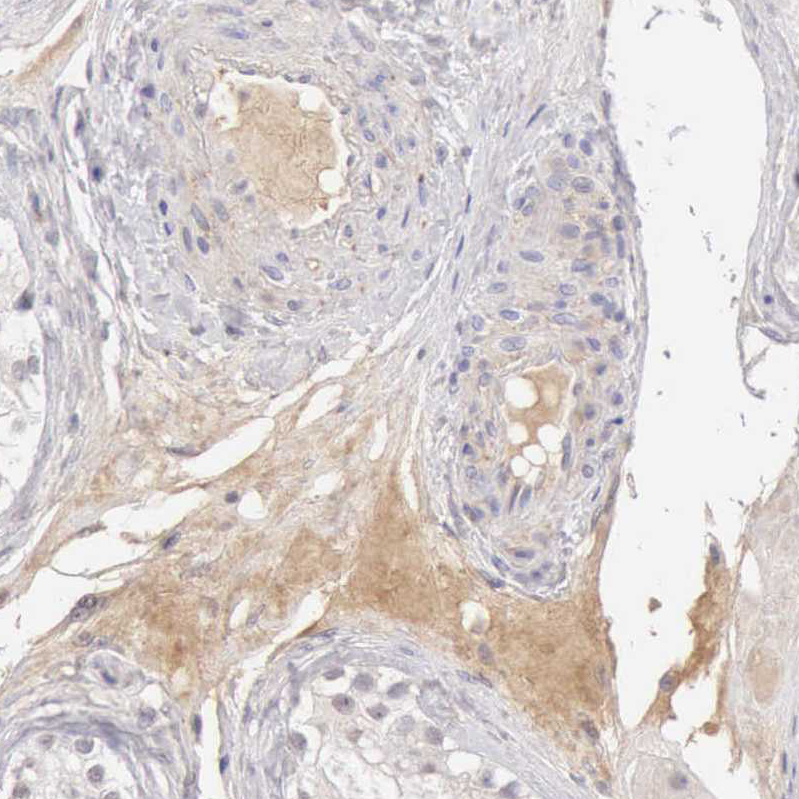

Immunohistochemical staining of human liver shows moderate positivity in erythrocytes.